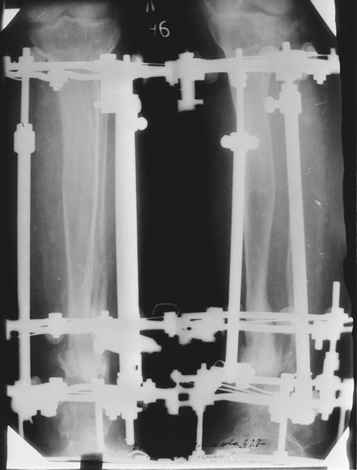

На втором этапе произведёно освежение краёв костных фрагментов б/б и м/б костей с приданием проксимальному фрагменту б/б кости впалой, а дистальному выпуклой формы, открытие канала проксимального фрагмента и погружной остеосинтез, а также остеотомия б/б кости в в/3 и м/б кости на границе с/3 и н/3 голени. Больной проводился одновременный бифокальный компрессионно-дистракционный остеосинтез. Достигнуто 11 см. удлинение и сращение ВПГ.

Срок лечения 11 месяцев. Наблюдение 2 года.